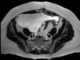

Ascites

Ascites is the abnormal buildup of fluid in the abdomen. Technically, it is more than 25 ml of fluid in the peritoneal cavity, although volumes greater than one liter may occur. [Source: Wikipedia ]